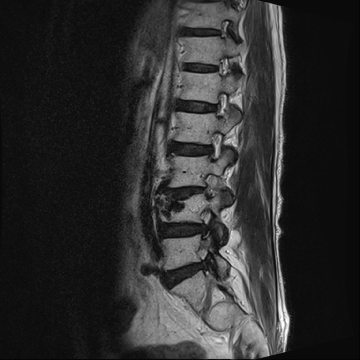

허리 디스크 수술 전·후

2021.10.19

2023.01.09

ㆍ환자 동의를 받은 자료이며, 이미지 사진은 실물과 다를 수 있습니다.

ㆍ모든 자료는 새움병원 자료입니다.